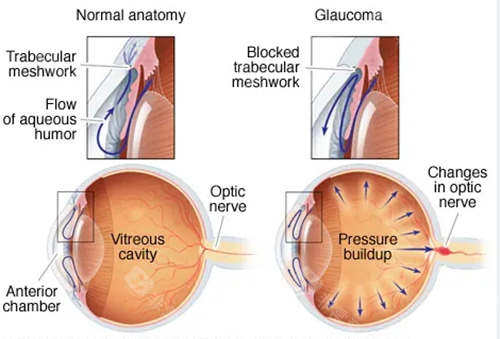

小梁切除术:针对开角型青光眼,通过改良缝合技术减少术后低眼压风险,单眼手术时长缩短至25分钟。

青光眼引流阀植入术:采用3D导航系统定位,植入比较准度提升,尤其适合难治性青光眼患者。

复合式小梁切除:结合抗代谢药物应用,手术可行性提升,尤其适合年轻患者。

激光虹膜边缘成形术:针对急性青光眼发作,10分钟内快速降低眼压,避免视力进一步损伤。

青光眼白内障联合手术:一次手术解决两种眼病,减少患者反复麻醉风险,术后视力修复周期缩短。

小创口青光眼手术(MIGS):通过微小切口植入iStent引流管,创伤小,适合早期青光眼患者。

前房穿刺术:针对急性青光眼眼压飙升,30秒内完成房水释放,快速缓解眼痛症状。

选择性激光小梁成形术(SLT):没有创口治疗早期青光眼,可重复操作,避免药物副作用。

个性化小梁切除术:根据角膜生物力学数据调整手术参数,术后散光发生率降低。

青光眼引流阀动态调节术:通过智能阀门控制房水流出量,避免术后眼压波动。